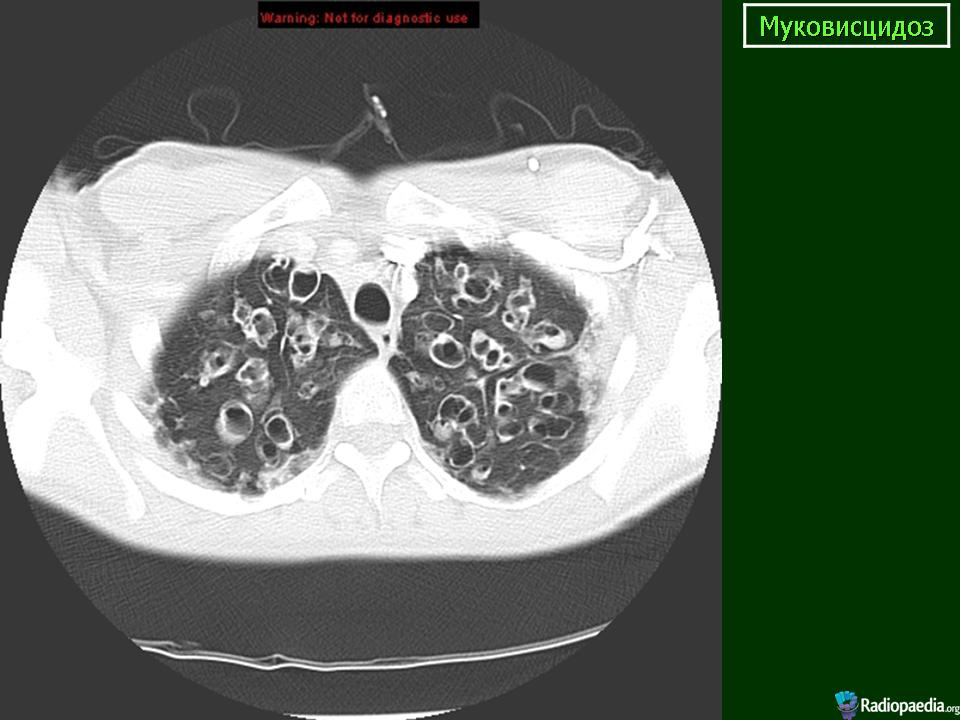

Муковисцидоз. Саркома мягких тканей. Метастатическое поражение легких.

На обзорной рентгенограмме органов грудной клетки в прямой и правой боковой проекции: легочный рисунок с обеих сторон усилен деформирован. Во всех отделах видны множественные разнокалиберные просветления, кольцевидные образования, очаги, фокусы уплотнения неоднородной структуры округлой, овальной или неправильной формы размерами от 0,5 см - 2,0 см диаметром до 4,0х1,5см. Корни легких уплотнены, от них отходят грубые тяжи.

Компьютерные томограммы. В легких с обеих сторон просветы бронхов расширены, деформированы, стенки их утолщены. Видны множественные цилиндрические, мешотчатые и веретенообразные бронхоэктазы, отдельные из которых заполнены секретом. Отмечается неравномерное утолщение междольковых перегородок, перибронхиального и периваскулярного интерстиция. В S10 нижней доли правого легкого, а так же в S9 и S10 нижней доли левого легкого выявляются метастазы в виде мягкотканой плотности округлой формы образований с четкими контурами.